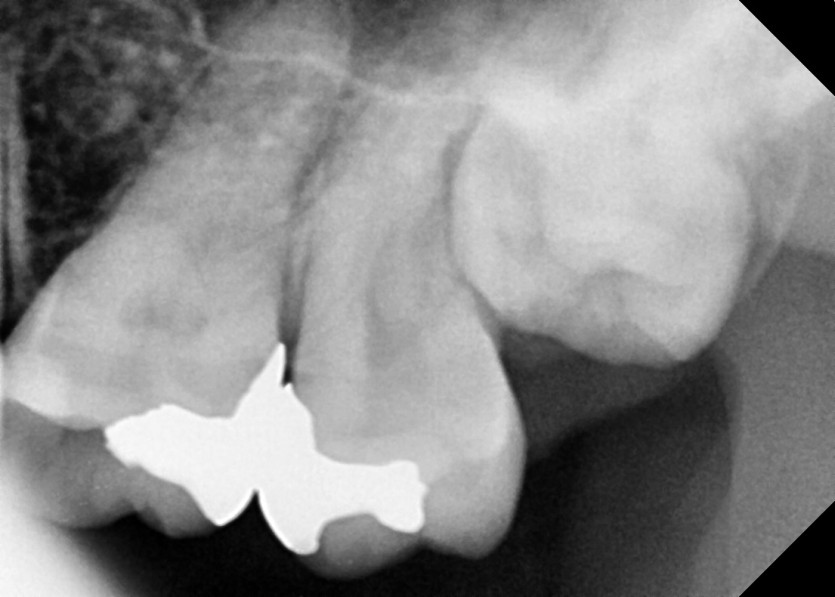

#28,38 사랑니 발치

구강 외과 전문의가 당일 발치했습니다.